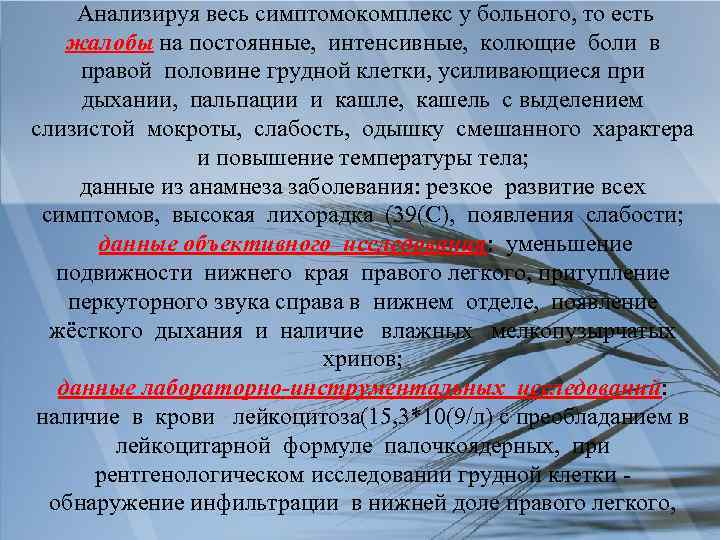

Анализируя весь симптомокомплекс у больного, то есть жалобы на постоянные, интенсивные, колющие боли в правой половине грудной клетки, усиливающиеся при дыхании, пальпации и кашле, кашель с выделением слизистой мокроты, слабость, одышку смешанного характера и повышение температуры тела; данные из анамнеза заболевания: резкое развитие всех симптомов, высокая лихорадка (39(С), появления слабости; данные объективного исследования: уменьшение подвижности нижнего края правого легкого, притупление перкуторного звука справа в нижнем отделе, появление жёсткого дыхания и наличие влажных мелкопузырчатых хрипов; данные лабораторно-инструментальных исследований: наличие в крови лейкоцитоза(15, 3*10(9/л) с преобладанием в лейкоцитарной формуле палочкоядерных, при рентгенологическом исследовании грудной клетки обнаружение инфильтрации в нижней доле правого легкого,

Мы можем выделить несколько главных синдромов: болевого, интоксикационного, дыхательной недостаточности.

Данные объективного и лабораторноинструментального исследований позволяют связать эти синдромы с поражением нижнего отдела правого легкого, характерного для пневмонии.